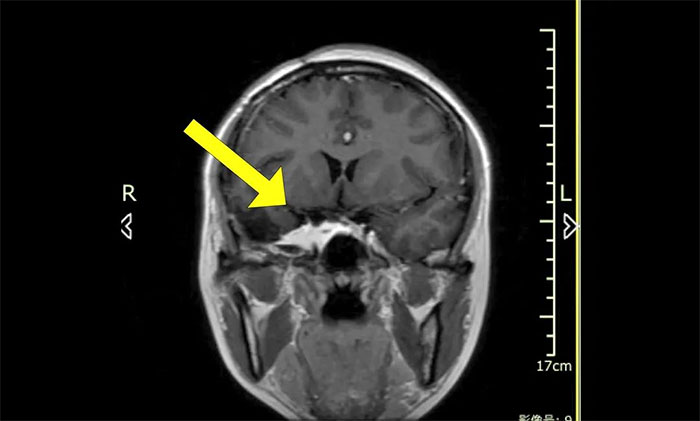

今年初医院收治了一位女性患者。该患者因突发视力模糊,头晕无法独立行走,在外院检查发现脑部右侧鞍旁肿块,手术病理诊断为海绵状血管瘤。

▲ 入院时MRI检查影像

肿瘤科(放疗)头部伽玛刀组陈琦主任完善检查并开展多学科评估讨论,其右侧鞍旁海绵状血管瘤与视神经等重要结构相邻,若不及时干预治疗,可因占位压迫进一步加重神经功能障碍,甚至导致失明。而该部位病灶的手术治疗难度高、风险大,术中可能对患者神经功能造成严重损害,应考虑采用创伤较小的伽玛刀治疗。